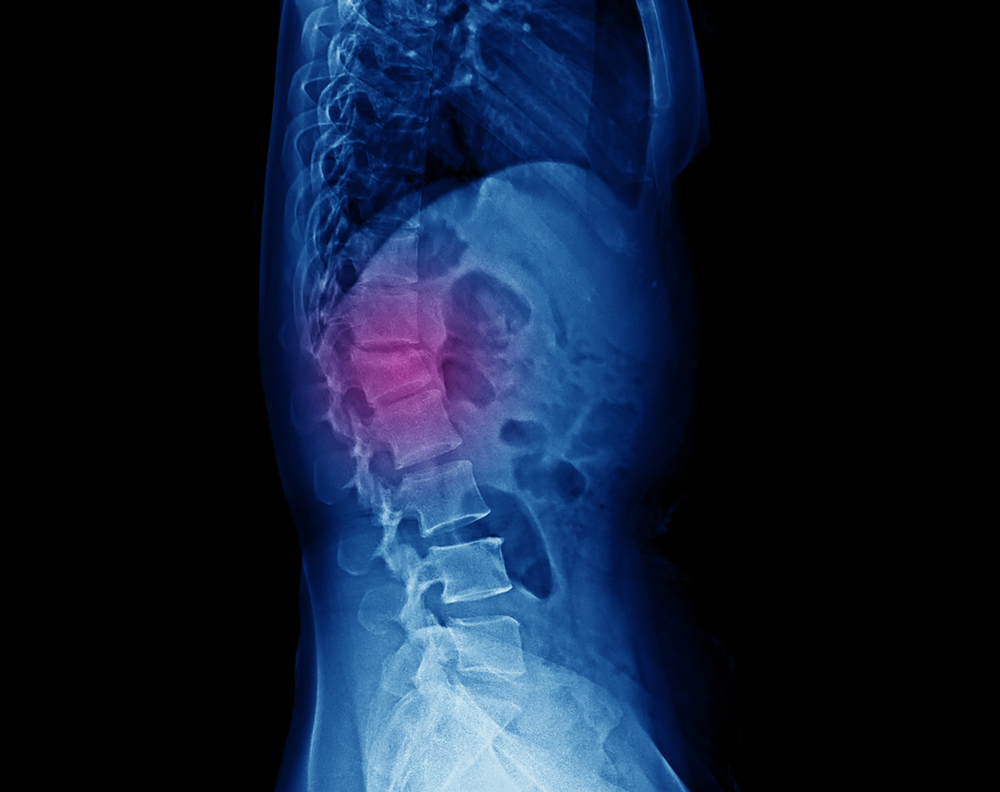

The spine is made up of vertebrae separated by discs that act as shock absorbers.

When these discs become compressed due to injury or wear and tear, it can result in

pain, numbness, or weakness in the back and legs.